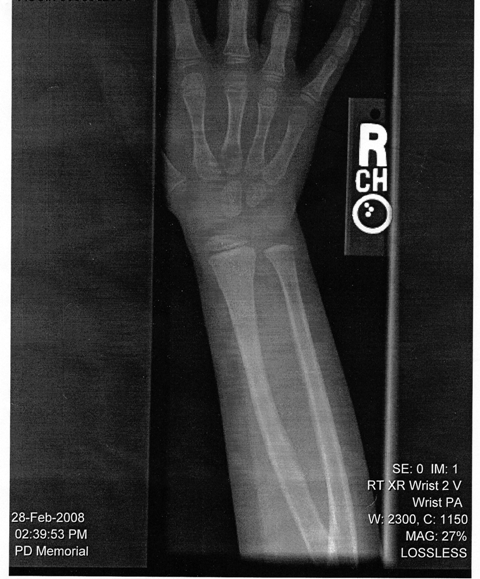

Can you spot the break? I certainly can’t

Last week Nancy sent the kids over to the playground for a few hours. They’ve been off track for a couple of weeks now and are driving Nancy nuts so she takes every opportunity to get them out of the house. When I got home from work, Sam was in house bawling that he hurt his arm. I don’t know how he fell but we’ve experienced enough broken arms in our child-raising adventures to think he likely had a buckle fracture based on the way he was holding his arm. It was getting kind of late to take him to the doctor that night and he wasn’t in too much pain so we decided to just give him some Tylenol and schedule an appointment with the doctor the next day. Man, it’s tough for a guy to get some sympathy when all of your sisters have had broken arms before you. Waiting also had the added benefit of being able to schedule Diana for the same time.

When he got back from the doctor Sam had a splint on his arm and a smile on his face. Apparently his break wasn’t severe enough to require a cast (bummer, I always like seeing what crazy color the kids pick for their casts) so they said to just leave it in the splint for several weeks. The biggest problem with the broken arm is that it’s his right arm and the splint they gave him limits the use of his fingers so he makes a mess at the dinner table. Maybe in another week we can trade out for a different splint – one that lets him use his fingers more.